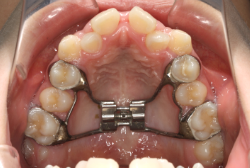

混合歯列期から治療開始した側方拡大による非抜歯症例

そこで、まず急速拡大装置を使用して上顎骨の拡大を行い、上顎骨の容量が拡大したことを確認後、マルチブラケット装置を使って全体の修正をする、と言う二段階の作戦をとることになりました。

急速拡大装置を1日1回装置の中央にある拡大ネジを、ご自身で回して頂くことで25日間くらいかけて、6mmほど拡大しました。拡大後は、上顎の前歯の隙間が広がっていることがお分かりいただけると思うのですが、土台の骨ごと広がるのでこのような隙間ができます。その後1年半くらいマルチブラケット装置を使用して、全体の修正を行いました。

結局、歯の本数を減らすことなく、すべてご自分の歯を残して正しい配列にすることができました。このケースの場合、2009年10月より拡大と経過観察を行い、2012年3月より1年2ヶ月マルチブラケット装置を装着、2013年5月に治療を終了しました。2段階で行う治療としては短期間で終了しているケースと思います。